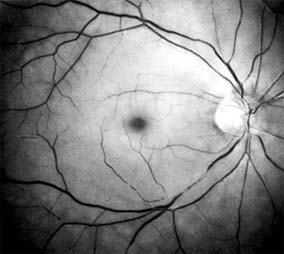

Ophthalmoscopically, the superficial retina becomes opacified except in the foveola, where a cherry-red spot is evident (Figure 10-27). The cherry-red spot is pigment of the choroid and retinal pigment epithelium viewed through the extremely thin overlying foveolar retina and contrasted with the thicker and translucent perifoveolar retina. Twenty-five percent of eyes with central retinal artery occlusion have cilioretinal arteries that spare macular retina and may preserve some central visual acuity. Clinically, the retinal opacification resolves within 4-6 weeks, leaving a pale optic disk as the major ocular finding. In older patients, giant cell arteritis must be excluded and if necessary treated immediately with high doses of systemic corticosteroids. Other causes of central retinal artery occlusion are arteriosclerosis and emboli from carotid or cardiac sources. These are discussed further in Chapter 15.

Figure 10-27: Acute central retinal artery occlusion with opaque white retina and attenuated vessels. (Courtesy of University of California, San Francisco.)